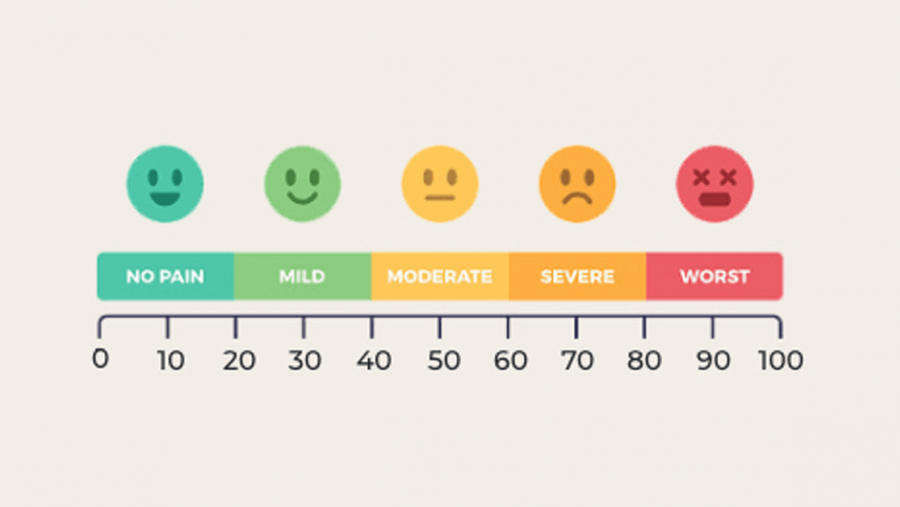

Researchers look for best ways to manage chronic low back pain based on people’s unique experience of pain

HEAL researchers develop roadmap for personalized chronic pain treatments based on patient preferences

Researchers are looking for ways to predict which individuals with pain can recover on their own and which don’t